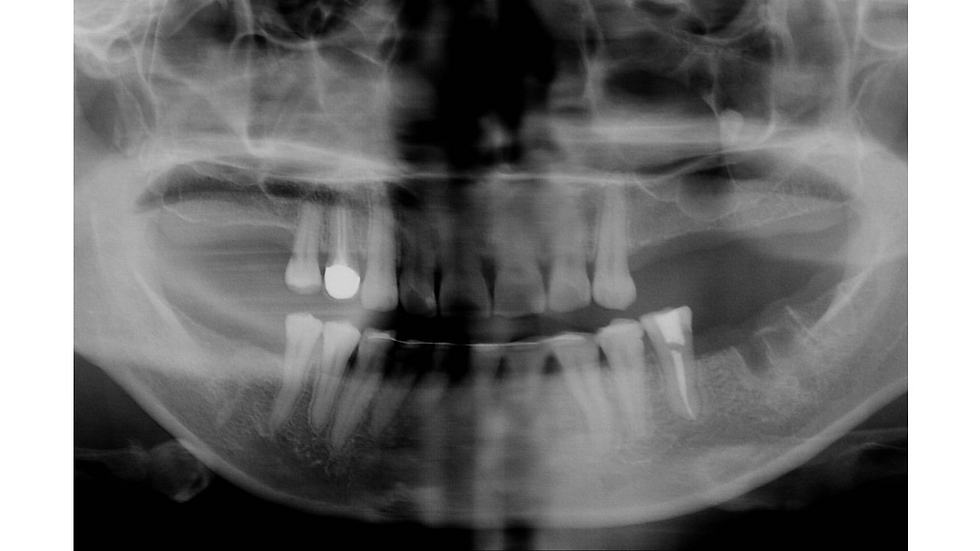

Panoramic x-ray: Multiple septa are seen in both right and left sinuses. Due to the amount of bone graft required, crestal approach for the anterior part and lateral approach for the posterior part of the sinus are preferred. In the posterior region, the number of implants required should match the number of missing teeth.

Panoramic x-ray after sinus graft and placement of implants.